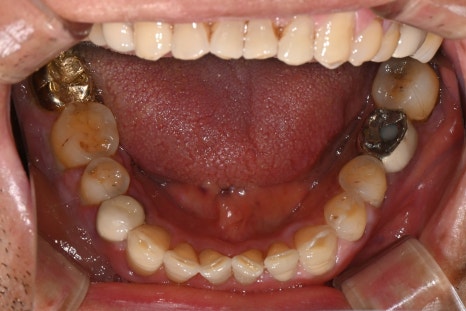

왼쪽은 초진 당시 촬영한 파노라마 엑스레이, 오른쪽은 환자분의 구강 내 사진입니다.

오른쪽 아래 어금니(#47)는 엑스레이에서 잇몸뼈가 많이 녹아 있었고 치아도 많이 흔들려, 전체 잇몸치료와 함께 #47 발치 & 임플란트 치료를 계획하고 있었습니다.

첫 내원 날, 단순한 검진과 스케일링 치료를 위해 방문하셨고

구강 내 육안상이나 엑스레이 상으로는 큰 문제는 보이지 않았습니다.

겉으로만 보면 치과에서 흔히 볼 수 있는 평범한 환자분처럼 느껴졌지요.

그런데 스케일링 도중 출혈이 예상보다 많고 지혈도 잘 되지 않아

가볍게 처치만 마친 뒤 일단 귀가하셨습니다.